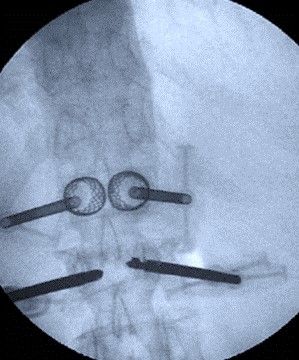

Vertbroplastika primenom stenta

Multisegmentna Vertbroplastika